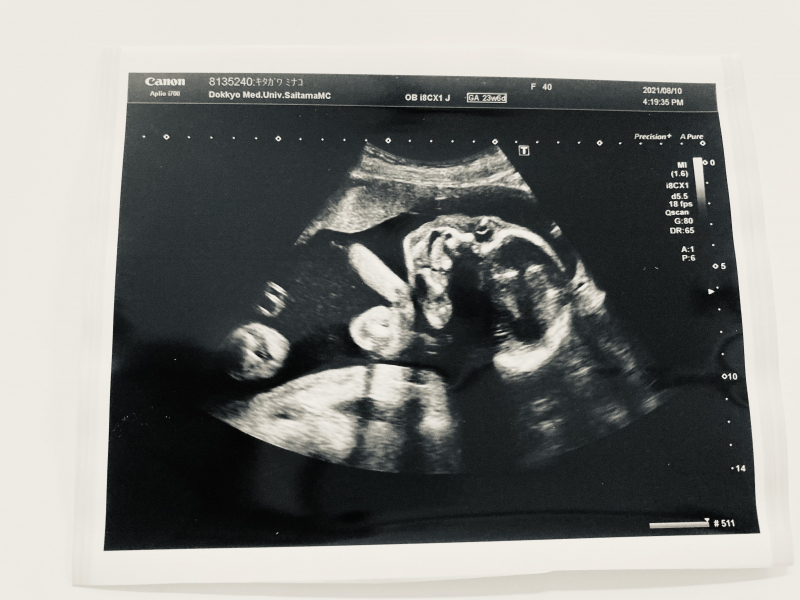

先日のエコーでよく見ると、口唇口蓋裂では?と不安に思えて仕方ありません。角度とかそういうのもあるのかもしれませんが、次回2週間後の検診まで気が気でなくて…どう判断されますか?

赤ちゃんのエコーで、口唇口蓋裂なのではないかとご心配をされているのですね。